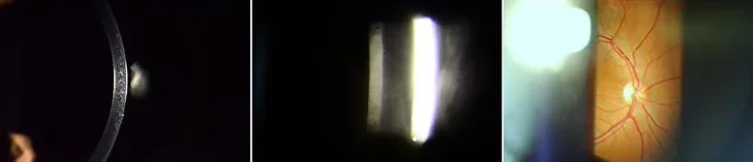

Microscope Type | Galileo Parallel |

Magnification Change Way | Drum Five Magnifications |

Total Magnifications | 6x,10x,16x,25,40x |

Eyepiece | 12.5x |

Diopter Adjustment | 5D~+5D |

Slit width | 0-14mm continuous |

Slit Height | 1-14mm continuous |

Light Spot Diameter | 0.2.1.2.5,10.14mm |